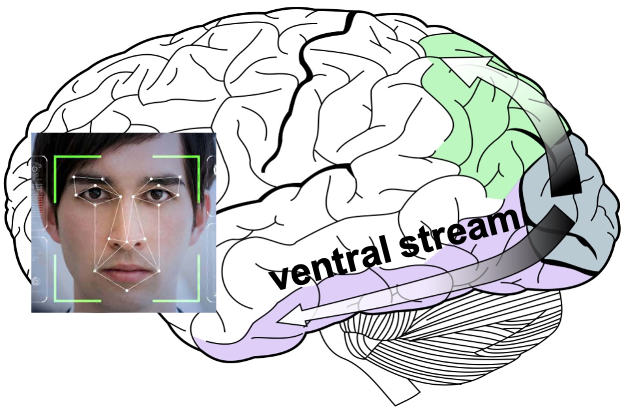

Some functional #neuroscience: Inf temp lobe is involved in higher order visual processing along the ventral stream (the "what is it" path of visual sensory processing https://abs.twimg.com/emoji/v2/... draggable="false" alt="➡️" title="Pfeil nach rechts" aria-label="Emoji: Pfeil nach rechts"> color/object/word/face/body perception/recognition/identification, & associated cognitive functions)

https://abs.twimg.com/emoji/v2/... draggable="false" alt="➡️" title="Pfeil nach rechts" aria-label="Emoji: Pfeil nach rechts"> color/object/word/face/body perception/recognition/identification, & associated cognitive functions)

color/object/word/face/body perception/recognition/identification, & associated cognitive functions)12/13" title="Some functional #neuroscience: Inf temp lobe is involved in higher order visual processing along the ventral stream (the "what is it" path of visual sensory processinghttps://abs.twimg.com/emoji/v2/... draggable="false" alt="➡️" title="Pfeil nach rechts" aria-label="Emoji: Pfeil nach rechts"> color/object/word/face/body perception/recognition/identification, & associated cognitive functions)12/13" class="img-responsive" style="max-width:100%;"/>

color/object/word/face/body perception/recognition/identification, & associated cognitive functions)12/13" title="Some functional #neuroscience: Inf temp lobe is involved in higher order visual processing along the ventral stream (the "what is it" path of visual sensory processinghttps://abs.twimg.com/emoji/v2/... draggable="false" alt="➡️" title="Pfeil nach rechts" aria-label="Emoji: Pfeil nach rechts"> color/object/word/face/body perception/recognition/identification, & associated cognitive functions)12/13" class="img-responsive" style="max-width:100%;"/>